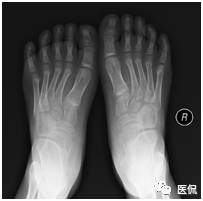

足部非负重正位片:足前部明显内收,跖骨远端及趾骨平铺,跖骨近端聚拢、外移;第1跖骨萎缩,第5跖骨肥大,密度增高;距骨扁而宽,距骨中轴线明显远离第1跖骨,跟骨内翻呈马蹄状,跟骨中轴线明显远离第5跖骨,跟距关节半脱位;跗骨形态失常,舟骨外侧发育较小,相应部分与距骨形成关节中创网,但距舟关节半脱位,跗骨关节间隙变窄;胫骨远端骨化中心外侧部分较内侧部分明显扁小。

因常规正位片踝部跟骨、距骨、跗骨及胫腓骨重叠较多,诸骨形态失常、变化较大,且测量误差增大,很小的位置改变即可改变足骨的关系,所以只要可能,正位、侧位片都应行负重位检查,但负重正位片受设备及投照的限制不易达到,因此角度的测量主要在负重侧位片上进行才更有价值。